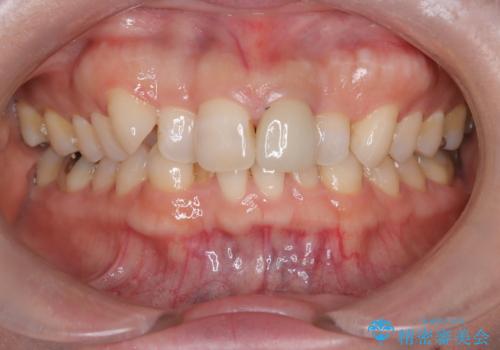

- 「八重歯をきれいにしたい」とのご希望で来院されました。診察の結果、上顎犬歯の萌出スペースが不足しており、典型的な八重歯(叢生)の状態でした。上下の歯の中心(正中)のずれや、奥歯のかみ合わせ(臼歯関係)のアンバランスも見られたため、単に見た目を整えるだけでなく、全体的な機能改善も必要と診断しました。